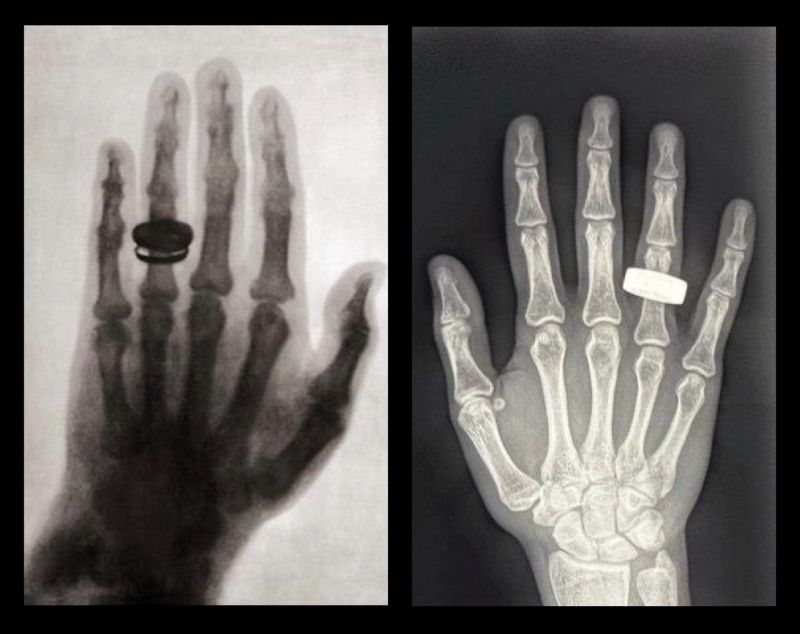

درست مانند اولین تصویر اشعه ایکس از ۱۳۰ سال پیش، این اسکن نمای سیاه و سفید یک دست را با یک حلقه نشان میدهد.

در سال ۱۸۹۵، ویلهلم رونتگن (Wilhelm Röntgen)، فیزیکدان آلمانی، به طور تصادفی پرتوهای ایکس را در حین آزمایش با پرتوهای کاتدی کشف کرد. او با شناخت پتانسیل پزشکی آن، اولین تصویر اشعه ایکس دست همسرش را با انگشتر گرفت. این تصویر واحد، تصویربرداری پزشکی را برای همیشه متحول کرد.

خدمه فرم ۲ آن پرتره اشعه ایکس را در ریزگرانش تقریبا در فاصله ۲۰۰ مایلی (۳۲۲ کیلومتری) بالاتر از سطح زمین بازسازی کردند. این تصویر در یک کپسول فضایی چهار نفره که با سرعت ۱۷۵۰۰ مایل در ساعت (۲۸۱۶۳ کیلومتر بر ساعت) حرکت میکرد، گرفته شده است.